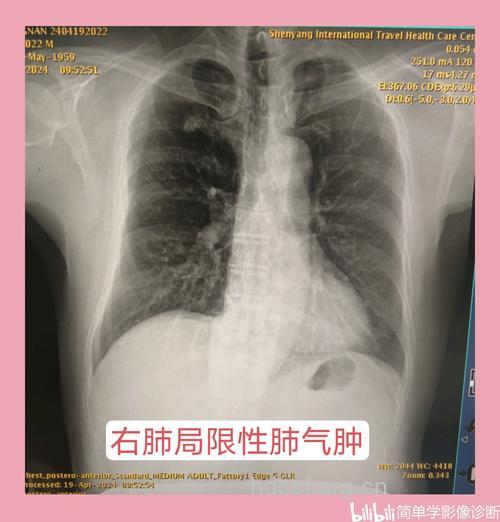

一、X线检查:

胸廓扩张,肋间隙增宽,肋骨平行,活动减弱,膈降低且变平,两肺野的透亮度增加。